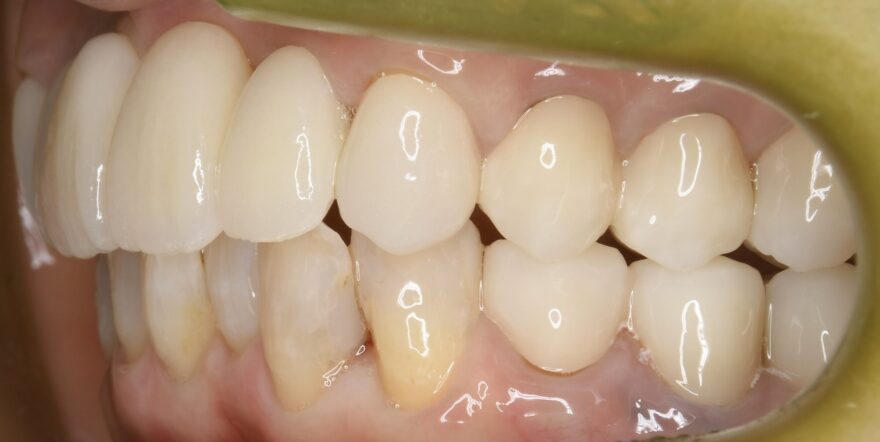

治療後の口腔内写真

白く輝く美しい歯が入りました。

長期にわたる理想的な噛み合わせが付与されました。

こちらにも、何でも噛める機能的なセラミック歯が入りました。。